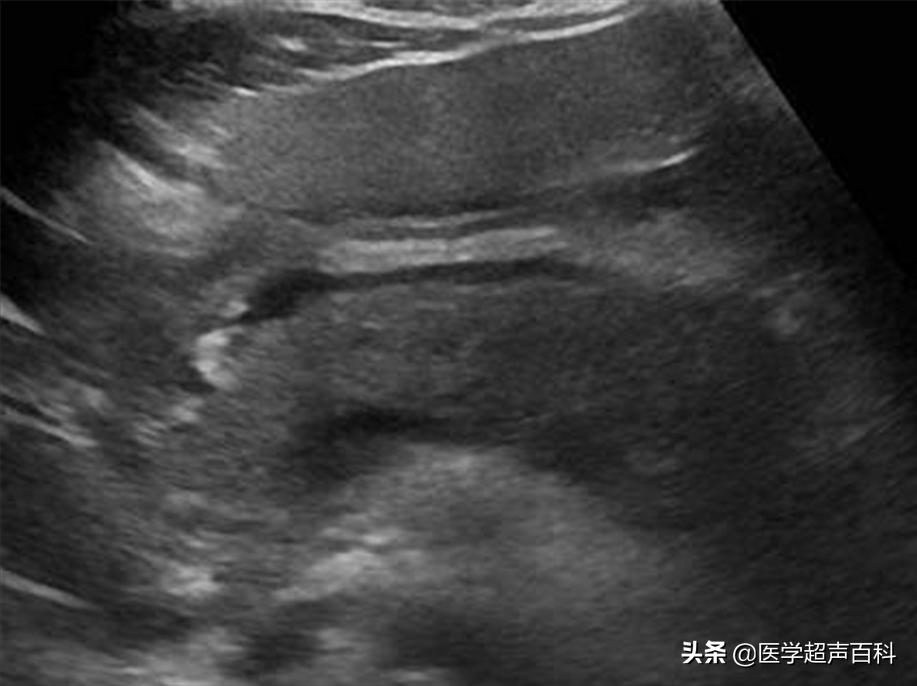

水肿型胰腺炎:胰腺弥漫性增大,边缘形态规整,内部回声减低,胰腺后方血管受压迫显示不清

急性胰腺炎声像图表现

(1)胰腺弥漫性或局限性增大,可失去正常形态,轮廓不清。

(2)内回声减低,呈弥漫分布的弱点状,中间有强弱不均、形态不整、边界不清的片状回声。严重水肿时呈透声暗区,似囊肿声像图。